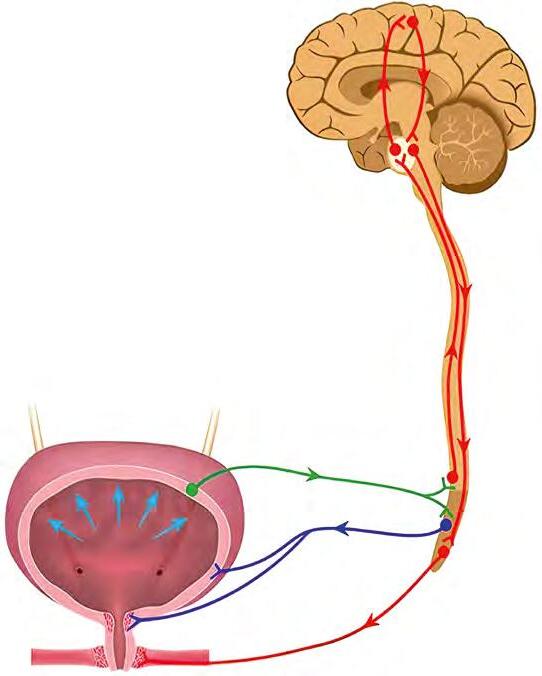

До вісцеральних рефлексів спинного

виділення, дефекації, статеві тощо, які регулюються на рівні крижових сегментів. Вони можуть контролюватися вищими відділами нервової системи.